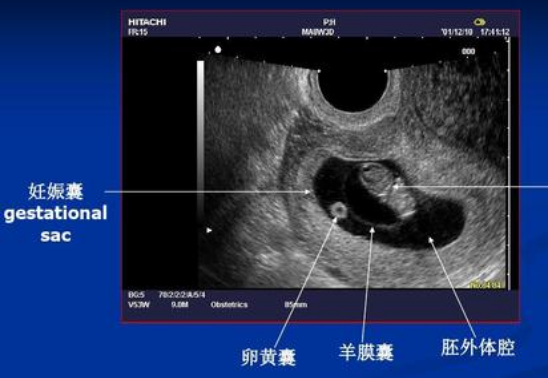

孕产期超声明白看 科室动态 医技科室

孕早期b超能告诉我们什么 知乎

孕期b超资料 4 8周详解 网易订阅

什么是胎囊 胎芽 胎心 知乎